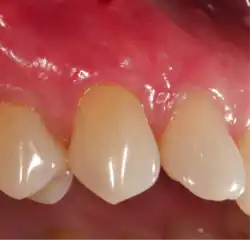

A free gingival graft is a dental procedure where a small layer of tissue is removed from the palate of the patient's mouth and then relocated to the site of gum recession. It is sutured (stitched) into place and will serve to protect the exposed root as living tissue. The donor site will heal over a period of time without damage. This procedure is often used to increase the thickness of very thin gum tissue.

A subepithelial connective tissue graft takes tissue from under healthy gum tissue in the palate, which may be placed at the area of gum recession. This procedure has the advantage of excellent predictability of root coverage,[19] as well as decreased pain at the palatal donor site compared to the free gingival graft. The subepithelial connective tissue graft is a common procedure for covering exposed roots.

Through the advent of micro-surgical procedures these procedures have become more predictable and comfortable for the patients. Gum grafts are usually performed by periodontists who are trained in these procedures, though general-purpose dentists may offer the procedures themselves. Outcome comparisons between both are highly variable, though with periodontists being specially-trained, periodontists generally recommend patients seeking their services over general-practice dentists. A literature review in 2018 showed that the amount of gum recession patients had was reduced after most types of root coverage periodontal surgery procedures. Reported unwanted outcomes were discomfort and pain, mostly related to the site where the tissue graft was taken.[27] This usually occurred in the first week after surgery and had no influence on root coverage outcomes. Currently, more research is needed to determine whether one root coverage technique is more effective than others.[27]